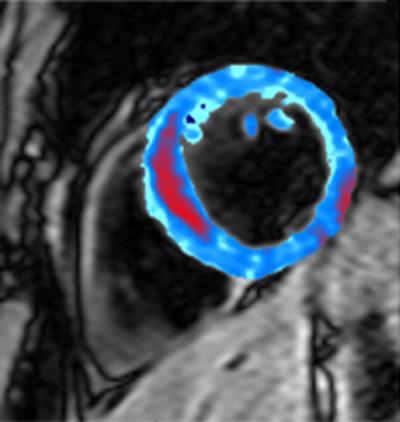

Images that for the first time show bleeding inside the heart after people have suffered a heart attack have been captured by scientists, in a new study published today in the journal Radiology .

The research shows that the amount of bleeding can indicate how damaged a person's heart is after a heart attack. The researchers, from the MRC Clinical Sciences Centre at Imperial College London, hope that this kind of imaging will be used alongside other tests to create a fuller picture of a patient's condition and their chances of recovery.

For the new small study, the researchers captured images of bleeding inside the heart in 15 patients from Imperial College Healthcare NHS Trust who had recently suffered a heart attack, using Magnetic Resonance Imaging (MRI). Analysis of the MRI scans revealed that the amount of bleeding correlated with how much damage the heart muscle had sustained.

Patients who had suffered a large heart attack, where a lot of the heart muscle was damaged, had a lot of bleeding into the heart muscle compared with those whose heart attack was relatively small.

The researchers were able to detect the area of bleeding because of the magnetic effects of iron, which is present in the blood.